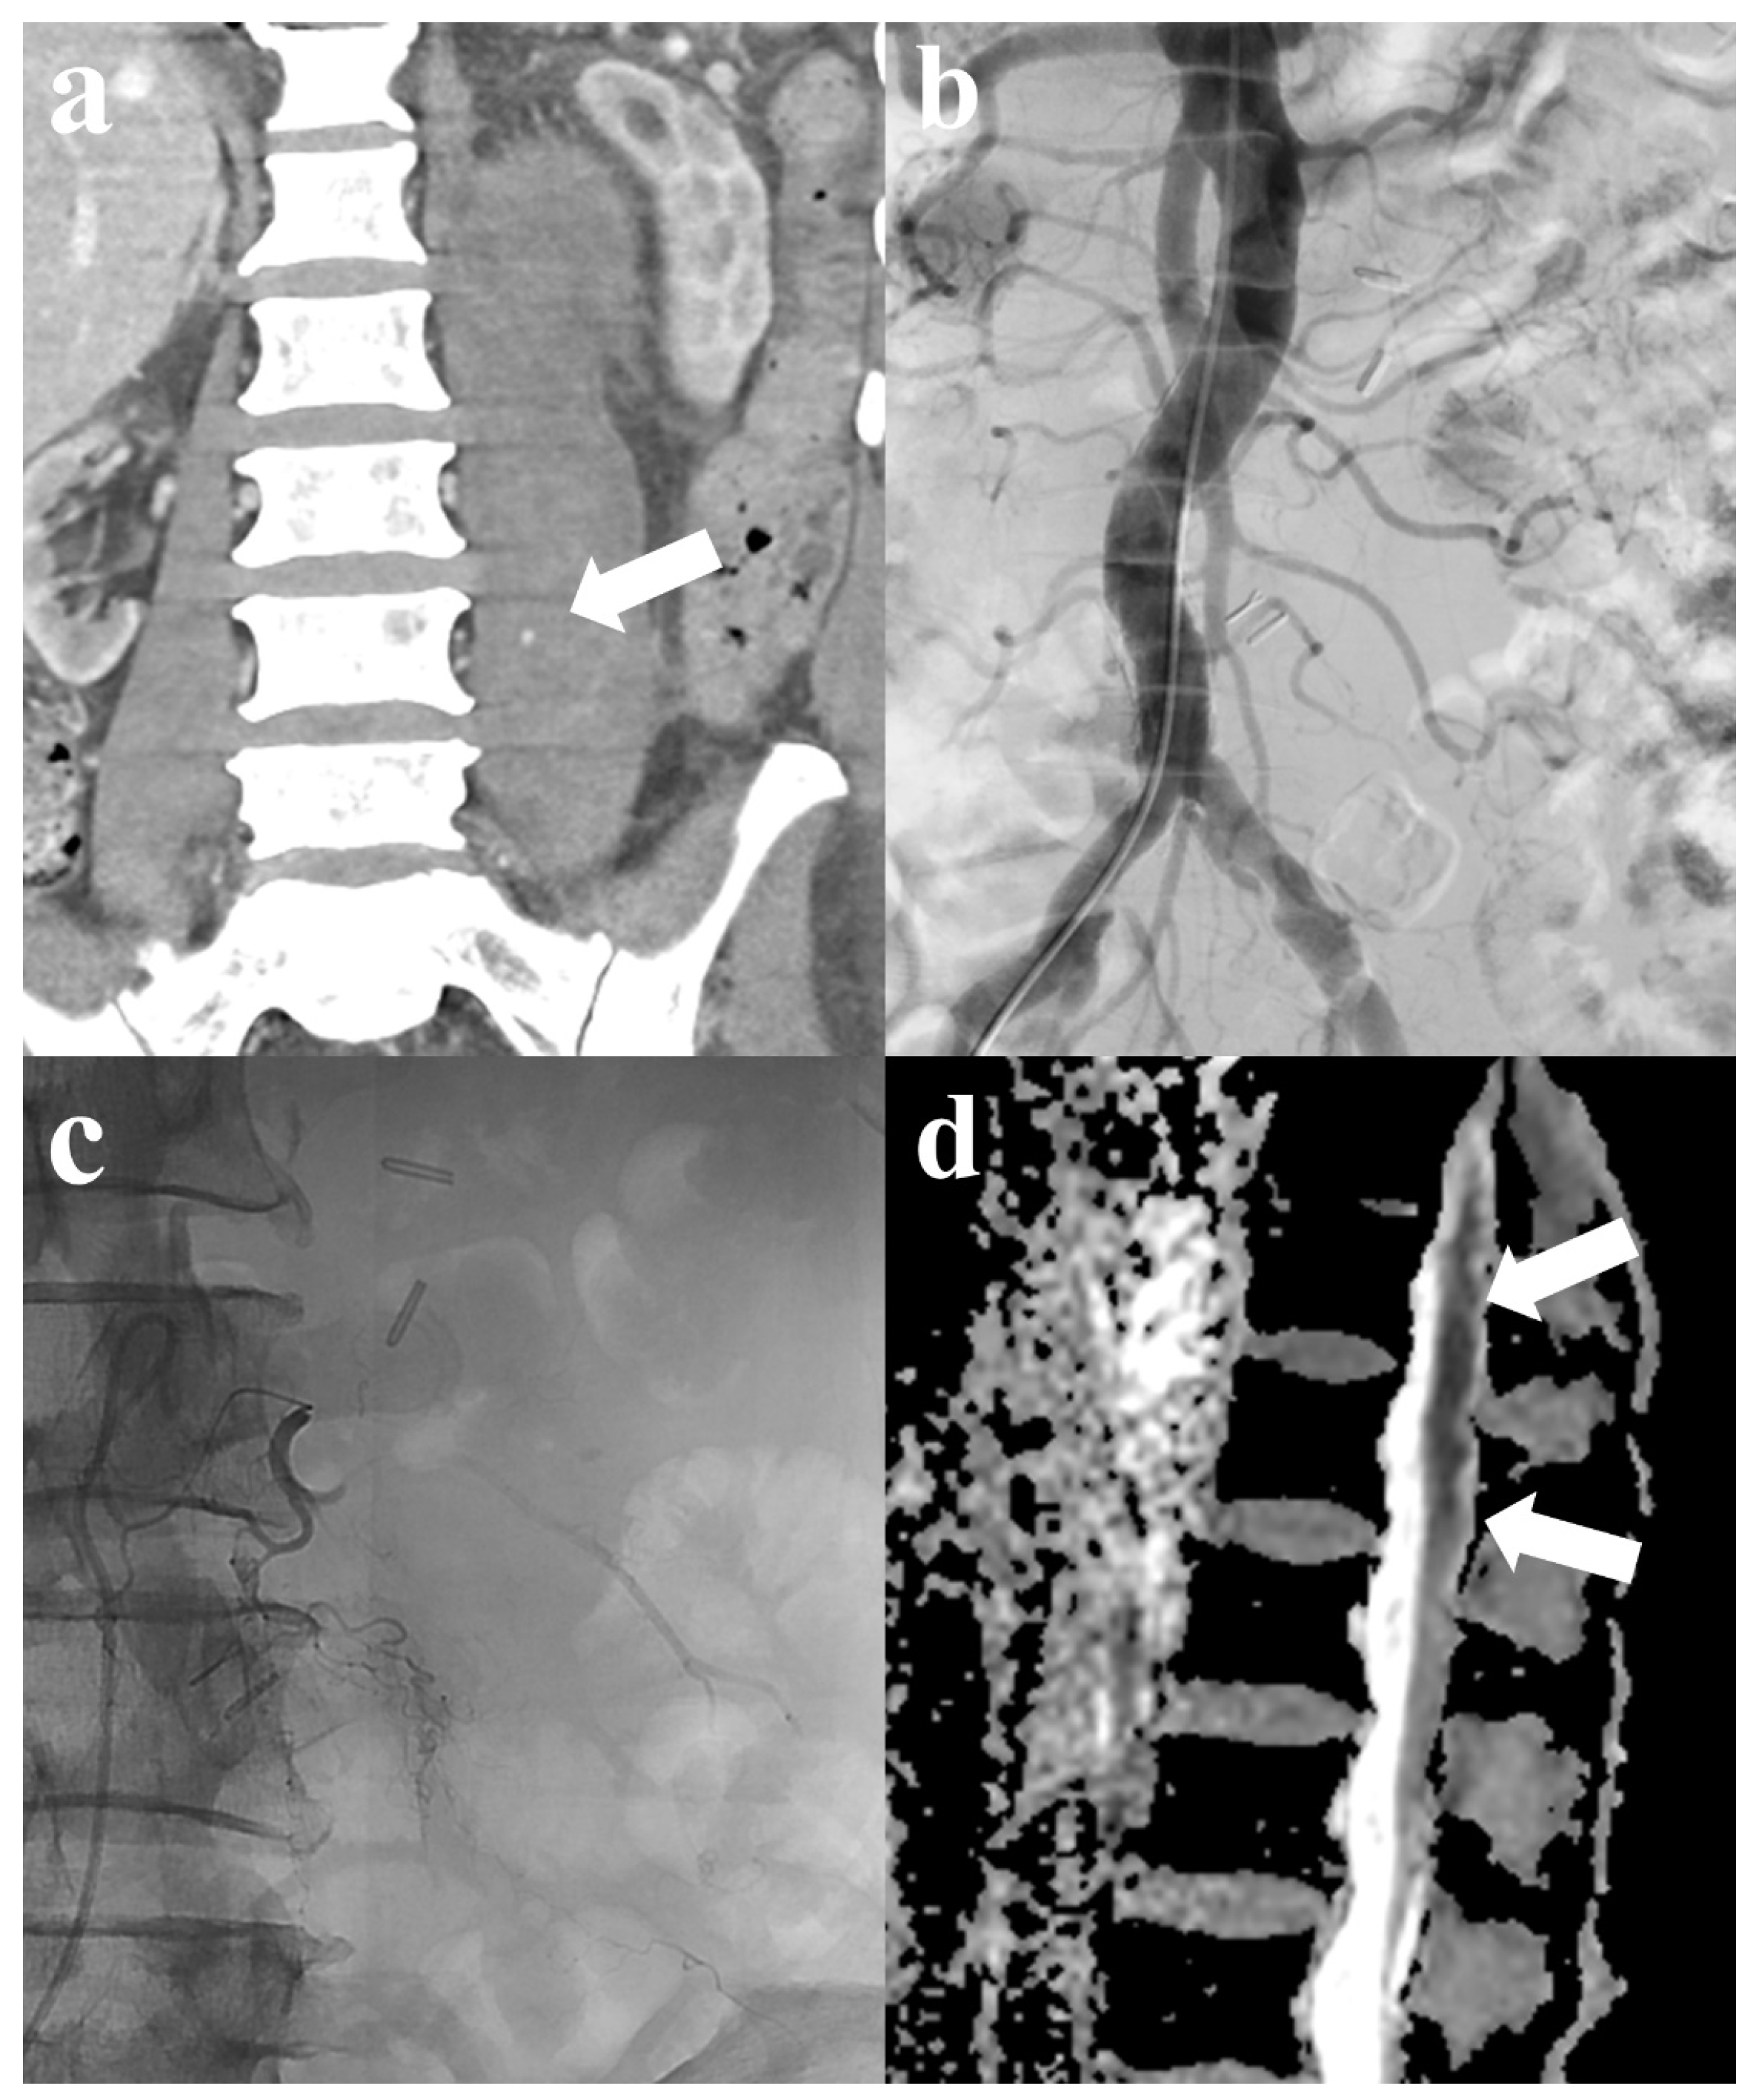

| F/44 | Liver cirrhosis | SG | N | 131 | 1.34 | Y/Y | Left 3rd and 4th lumbar artery; deep circumflex iliac artery | 4 | 9 | Y | 20 | N | |